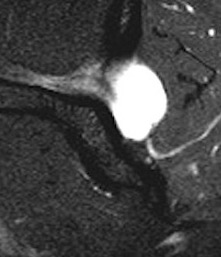

MRI

Spinoglenoid cyst

Spinoglenoid cyst with SLAP tear and posterosuperior labral tear